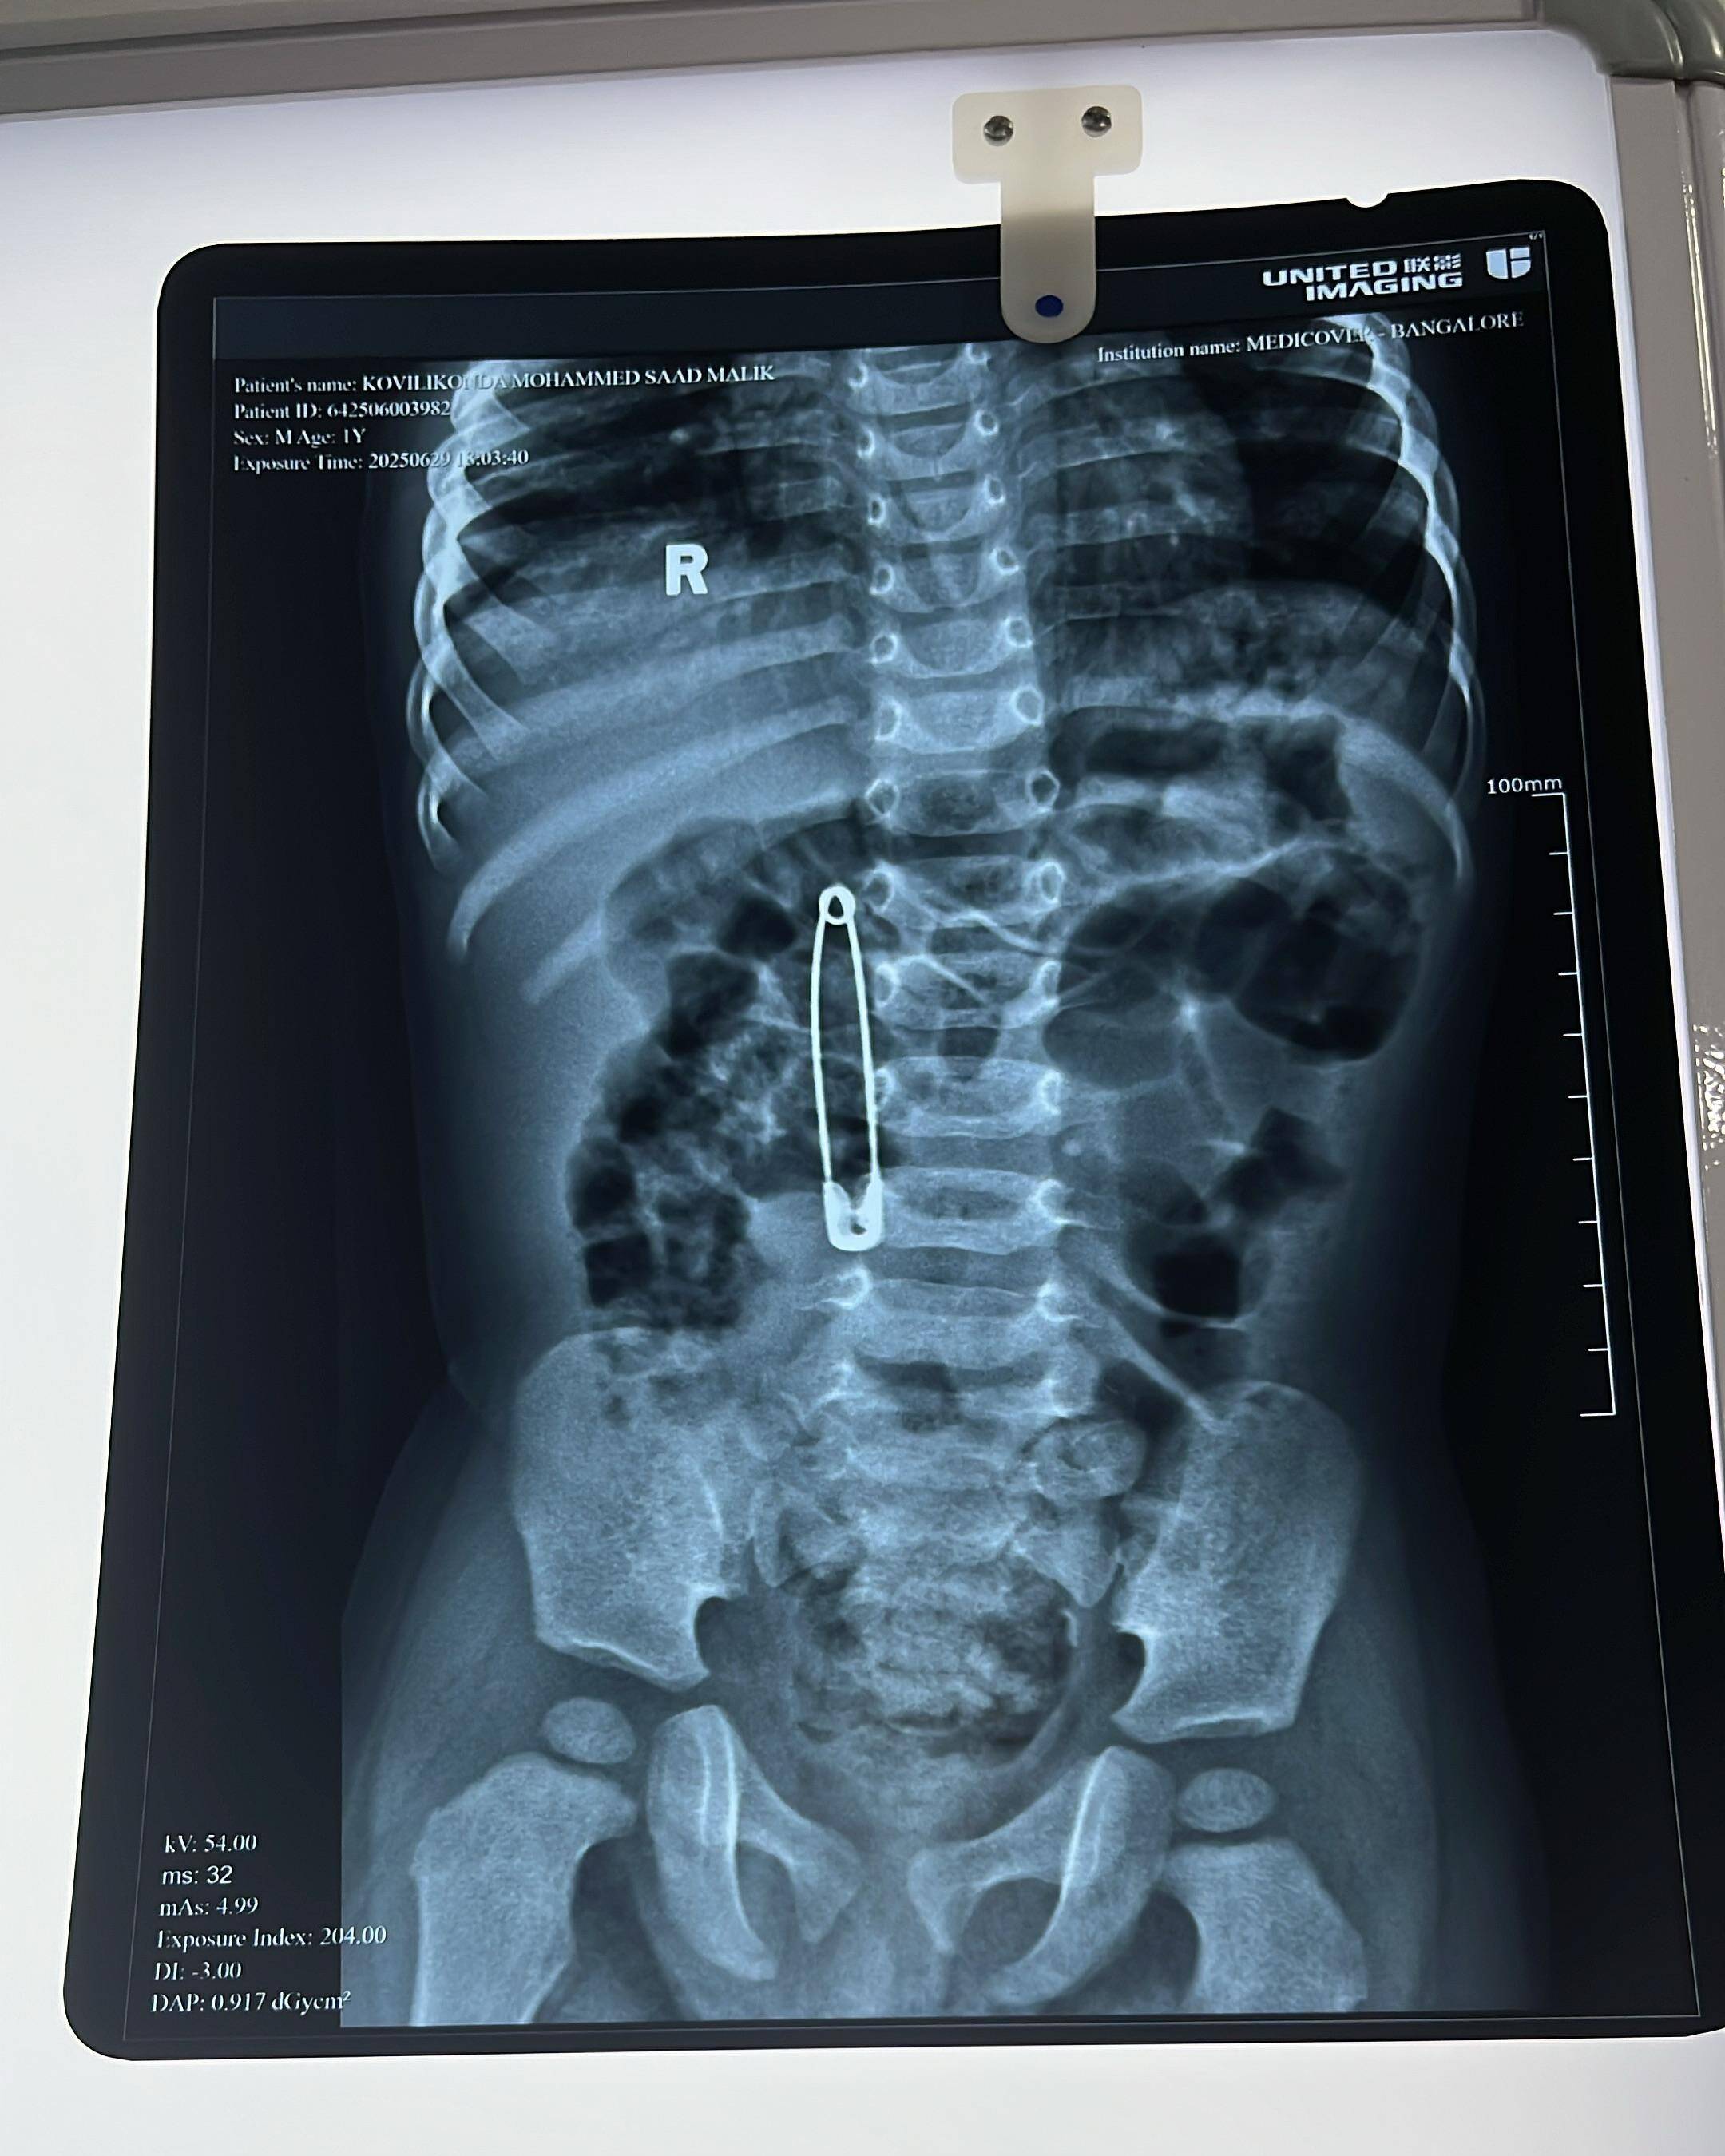

- X-ray confirmed the presence of a foreign metallic object (safety pin) in the gastrointestinal tract

- Diagnosis: Accidental ingestion of sharp metallic object โ safety pin